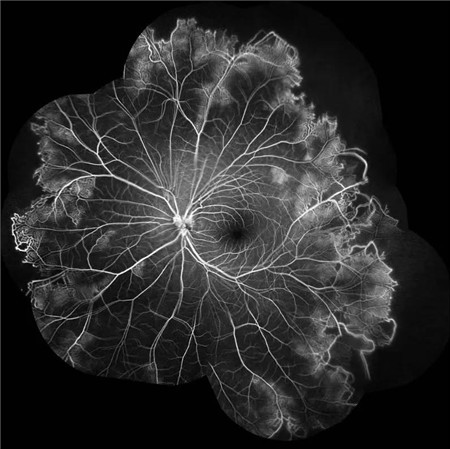

经过详细的眼底检查后,患者被诊断为IRVAN综合征引起的右眼黄斑裂孔,张风院长带领医生团队为患者施局右眼玻璃体切除+剥膜+眼内光凝+气液交换手术,经过半个月的恢复,患者右眼术后视力由术前0.3-达到0.6-的状态,且裂孔呈逐渐闭合状态。

视盘附近的动脉和动脉分叉处出现瘤样动脉扩张,视盘充血,边界不清,引起视盘周围视网膜内硬性渗出;视盘周可有少量放射状出血。

静脉不规则扩张和血管鞘膜,周边部小血管广泛闭塞,交界处毛细血管扩张和异常吻合。

严重者可发生从周边到黄斑的血管闭塞和缺血、玻血、新生血管性青光眼,最终视神经萎缩。